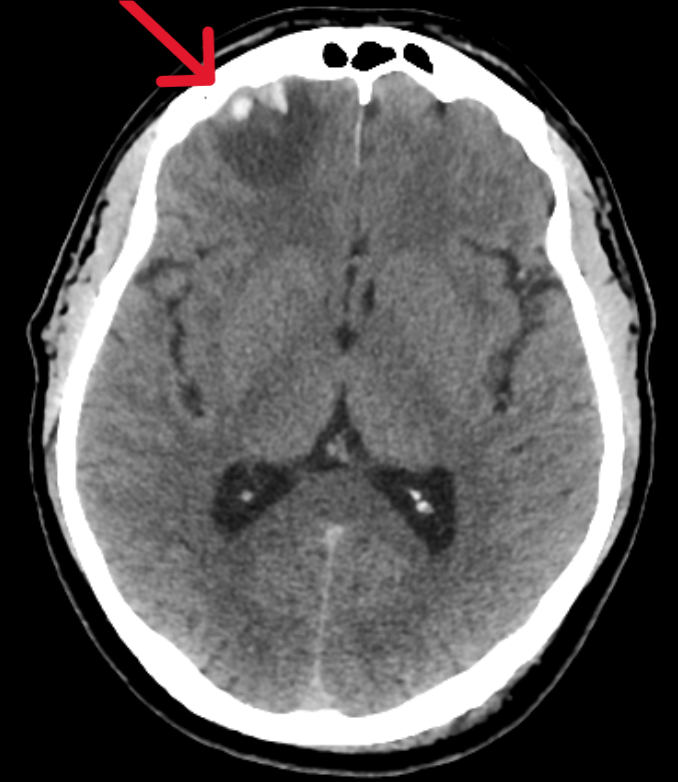

Пациент обратился в Ильинскую больницу, где была проведена компьютерная томография головного мозга и выявлены следующие изменения:

• перелом затылочной кости слева (то место, куда пришелся удар при падении);

• ушиб (контузия) мозга с геморрагическими включениями в правой лобной доле (противоположная от удара сторона).

Такой механизм травмы обусловлен тем, что мозг имеет подвижность внутри черепной коробки и после первого удара «отскакивает» и ударяется о противоположную стенку черепа.